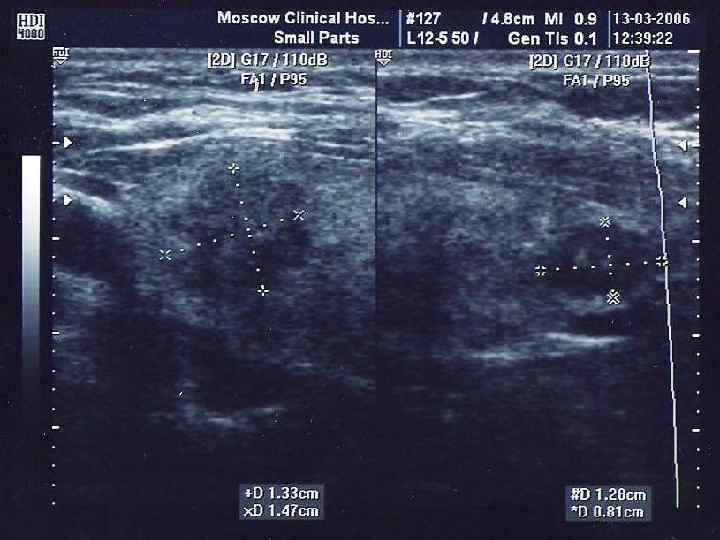

УЛЬТРАЗВУКОВОЕ ИССЛЕДОВАНИЕ